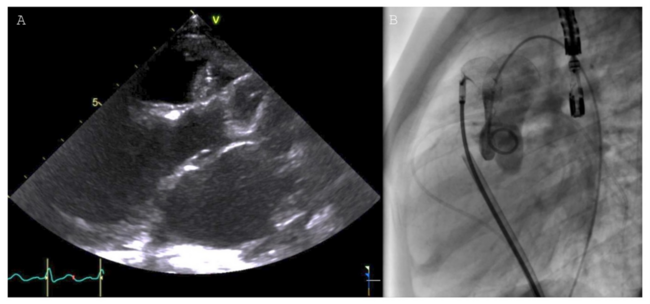

A cardiac catheterization with a vasodilation test was performed. Through transoesophageal echocardiography guidance, an 18-mm Figulla Flex occluder (Occlutech) was implanted with mild residual shunt (Figure). The mean PAP and PVRi was significantly reduced with the use of inhaled nitric oxide (0.11 WU.m2). Despite the residual shunt and aortic protrusion, the device was released without significant obstruction. The patient was started on sildenafil (20 mg/3 times a day). Five months later, a catheterization showed improved hemodynamic (Qp:Qs of 1.4:1, PVRi of 2.1 WU.m2), enabling successful surgical repair and device removal. Postoperative echocardiography showed normal PAP. After an uneventful postoperative course, the patient was discharged at postoperative day 5.